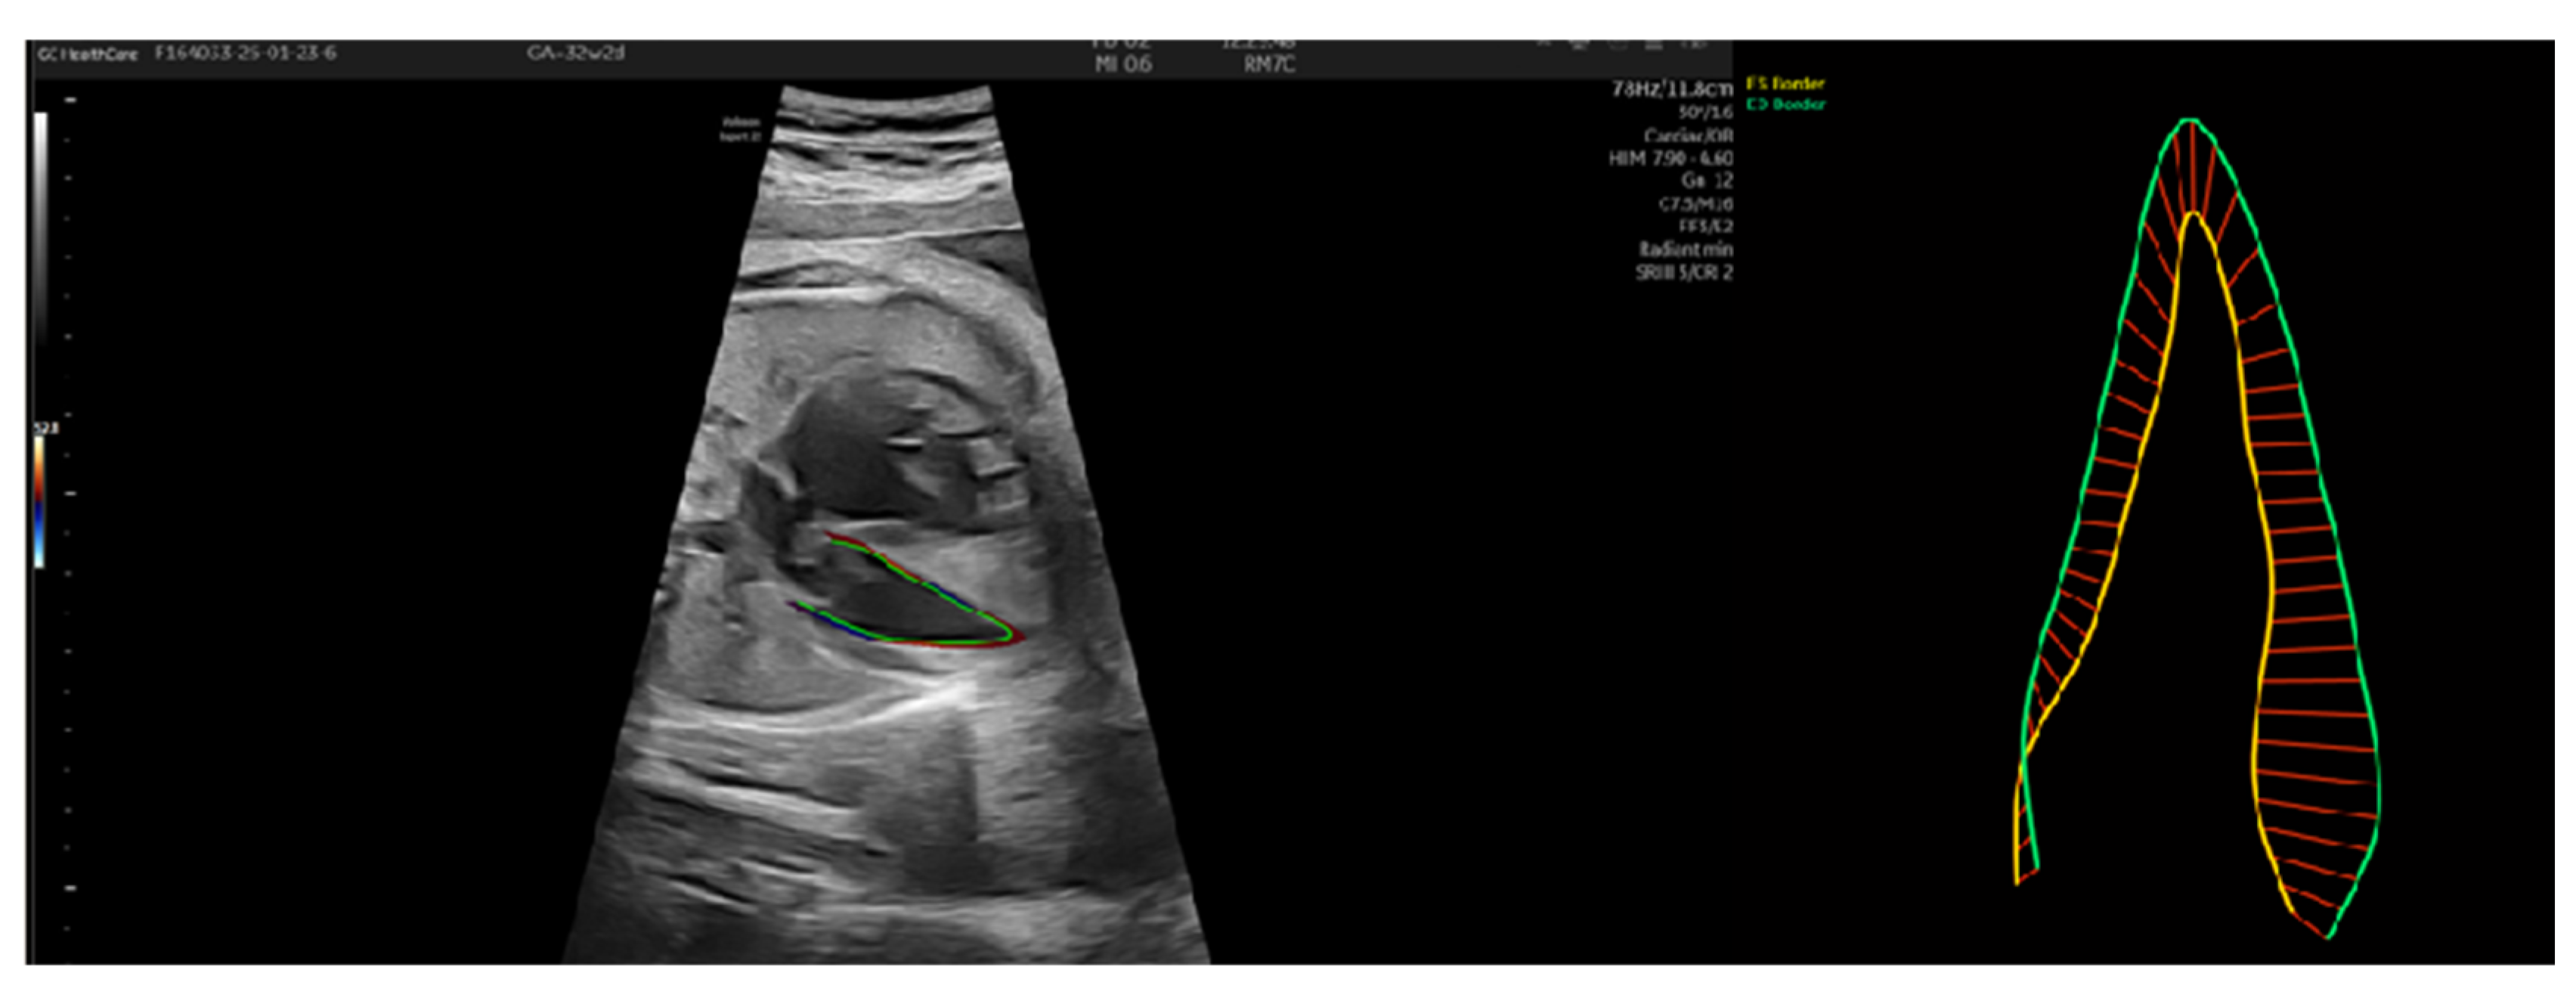

3.2. Patient Number 2

| Patient Number 2 | 27 Weeks | 29 Weeks | 32 Weeks 2 Days | 32 Weeks 4 Days |

|---|---|---|---|---|

| UA IP | 1.98 | 1.81 | 1.77 | 1.2 |

| UA IR | 0.72 | 0.86 | 0.82 | 0.83 |

| reverse flow UA | no | no | no | no |

| MCA IP | 1.94 | 2.22 | 1.64 | 1.98 |

| MCA IR | 0.86 | 0.88 | 0.8 | 0.83 |

| DV IP | no | no | no | 0.83 |

| right Ut A IP | no | no | no | 0.95 |

| left Ut A IP | no | no | no | 1.72 |

| LV endo GLS % | 14.01 | −19.01 | −13.27 | −10.14 |

| EF % | −32.93 | 64.4 | 63.8 | 49.57 |

| LV EDA cm2 | 0.91 | 1.4 | 1.95 | 1.32 |

| LV ESA cm2 | 1.13 | 0.76 | 1.08 | 0.83 |

| LV ESL cm | 1.59 | 1.31 | 2.27 | 1.85 |

| ESD bas cm | 0.97 | 0.84 | 0.88 | 0.87 |

| LV ESD mid cm | 0.73 | 0.61 | 0.53 | 0.48 |

| LV EDL cm | 1.42 | 1.54 | 2.59 | 2.03 |

| LV EDD bas cm | 0.93 | 1.1 | 0.95 | 0.81 |

| LV EDD mid cm | 0.73 | 1 | 0.9 | 0.78 |

| LV EDV mL | 0.51 | 1.08 | 1.37 | 0.75 |

| LV ESV mL | 0.68 | 0.38 | 0.5 | 0.38 |

| MAPSE l (lateral mitral annulus) cm | 0.13 | 0.25 | 0.41 | 0.21 |

| MAPSE s (septal mitral annulus) cm | 0.22 | 0.27 | 0.23 | 0.14 |

| FAC (fractional area change) % | −24.7 | 45.72 | 44.36 | 36.99 |